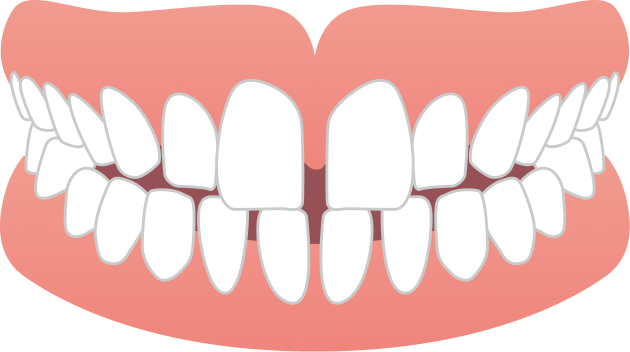

40代女性 前歯のガタガタが気になる

40代女性の患者さまで、前歯のガタつきを主訴にご相談に来院されました。マスクを外す機会が増えたことで歯並びが気になるようになり、また周囲で矯正治療をされた方がいらしたこともきっかけとなり、治療をご検討されたそうです。見た目が目立たず、できるだけ痛みの少ない方法で治療を進めたいというご希望をお持ちでした。

BEFORE

| 主訴 | 前歯のガタガタが気になる |

ガタガタ・八重歯